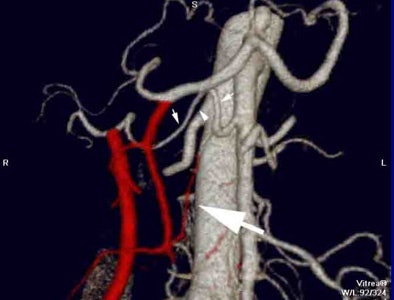

![]() |

| Color-encoded angiogram shows an aberrant origin of the right hepatic artery from the superior mesenteric artery (small arrows). As this does not cross through the surgical plane, it is not encoded although documenting its presence preoperatively is important. There is an aberrant origin of a superior pancraticoduodenal artery from this right hepatic artery (large arrow) that is predicted to traverse the surgical plane and which is subsequently color-encoded. |

The radiologist generates VR maps which are color-coded. All vessels that cross through the anticipated surgical field are color-coded in red. The finding that 40% of patients have a relevant variant, and that those with a variant had increased blood loss are key, he said.

| There are multiple complete and incomplete pancreaticoduodenal arcades traversing the surgical plane which are fed from the celiac axis and from various jejunal branches from the SMA. These arteries are color-encoded in red. This patient's operation was complicated by delayed bleeding requiring re-exploration. |